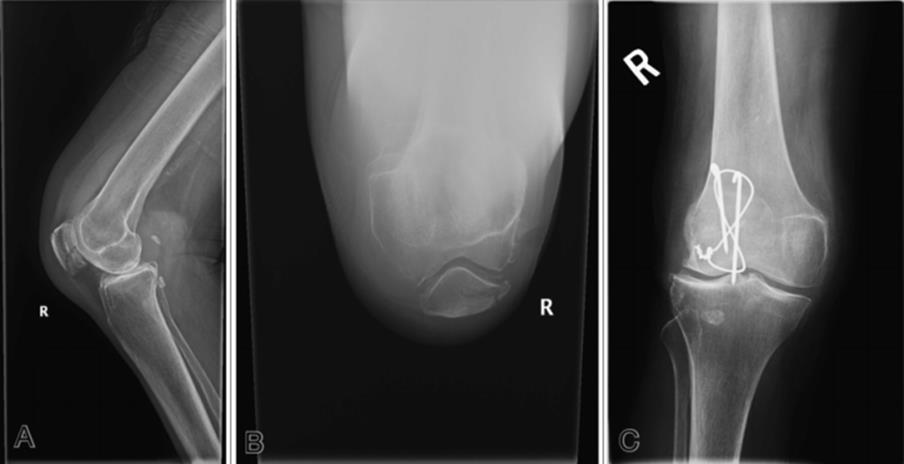

· On plain films, tibial plateau fractures can be radiographically occult; radiographically subtle; or clearly seen (Figure 4.9, Figure 4.10, Figure 4.11, Figure 4.12)

Figure 4.11 AP (A) and lateral (B) views of young cyclist struck by a car. Note the effusion seen on the lateral view, the vertical proximal tibial fracture, and the possible depressed tibial plateau fracture. CT (C) of same knee demonstrating the tibial plateau fracture. (Images courtesy of Arun Sayal, MD.)

Figure 4.12 A comminuted tibial plateau fracture. (Image courtesy of Arun Sayal, MD.)